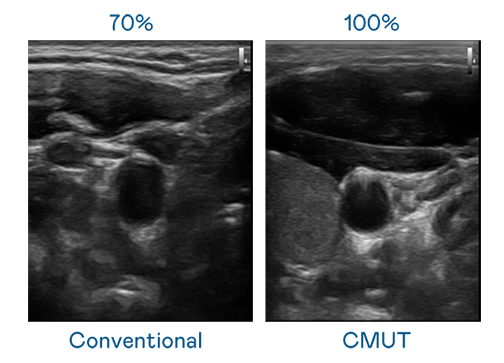

CMUT 技术是一种用电容式微机电元件来产生超音波讯号的技术。与传统 PZT 压电式技术相比,CMUT 频宽增加 30%,更宽频的超音波讯号让影像解析度大幅提升,是实现高影像品质医疗超音波扫描、促进精准医疗发展的关键技术。

大频宽带来超清晰影像

超音波影像的解析度高低,首先取决于探头能发出的讯号频宽。红宝石hbs9988 CMUT 可提供高清晰的超音波讯号,提供高频宽、高灵敏度、影像纹理细节更高的超音波影像,协助医护人员缩短影像判读时间及利用精准的医疗影像进行诊断。